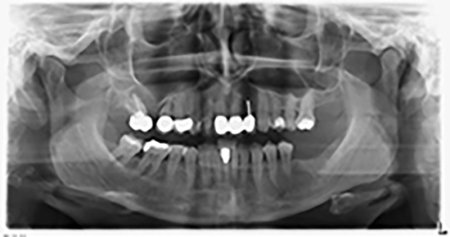

Etwa sechs Monate nach Extraktion der Zähne 16 und 14 wurde zur Planung und Risikominimierung eine digitale Volumentomografie (DVT, Planmeca) erstellt. Hierbei wurde deutlich, dass der Knochen sich nicht in der gewünschten Quantität regeneriert hat (Abb. 2 bis 7).

Abb. 2 bis 7: DVT mit stark reduziertem horizontalen Knochenangebot.

Um eine festsitzende Versorgung auf mindestens zwei Implantaten zu gewährleisten, ist eine Sinusbodenelevation sowohl in Regio 16 als auch in Regio 14 erforderlich. Da in diesem Fall das Restknochenangebot extrem gering ist, müsste ein verhältnismäßig großer Knochenaufbau durchgeführt werden. Große Knochenaufbauverfahren sind invasiv, mit einer höheren Patientenmorbidität verbunden, zeitintensiv und kostspielig. Die Vorhersagbarkeit der Behandlungsresultate ist geringer und das Misserfolgsrisiko höher. Vor dem Hintergrund dieser Nachteile, wurde die Patientin über eine herausnehmbare Alternative aufgeklärt, die sie jedoch konsequent ablehnte.